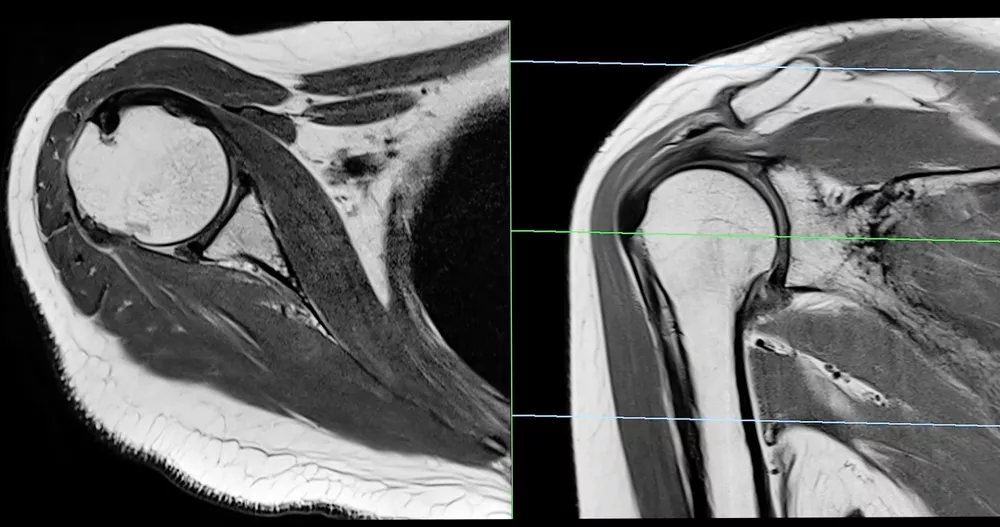

Especialización en imagen musculoesquelética

Contamos con estudios avanzados para la evaluación precisa de huesos, articulaciones y tejidos blandos, orientados al diagnóstico de lesiones deportivas, degenerativas y traumáticas.

Resonancia Magnética Articular

Diagnóstico de lesiones de rodilla, hombro, columna y otras articulaciones.

Evaluación de Lesiones Deportivas

Análisis detallado de músculos, tendones y ligamentos.